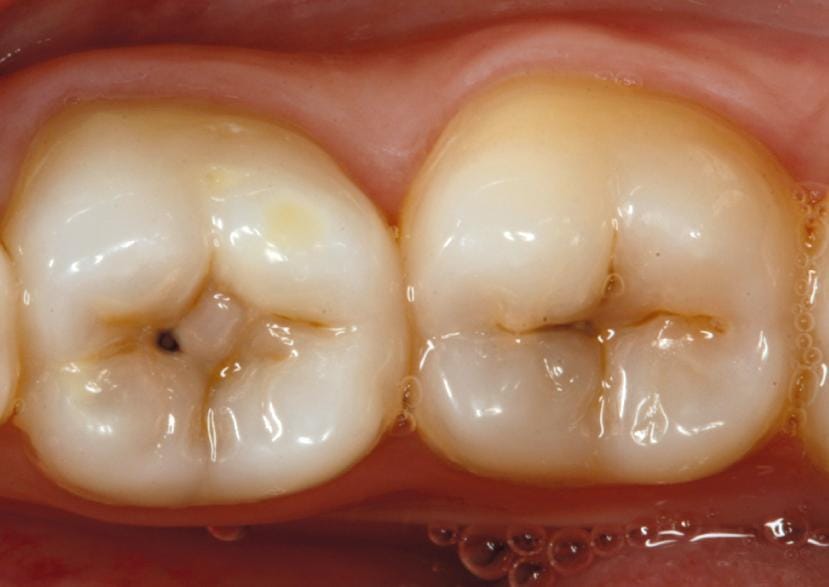

De acordo com o especialista, a cárie sempre começa de forma discreta, mas tende a evoluir com o passar do tempo quando não é tratada. “O risco maior é a perda do dente. A cárie começa pequena e, conforme você não resolve o problema, ela vai aumentando”, explica.

Com o avanço da lesão, as consequências vão além do desconforto inicial. “O paciente pode ter dor, inflamação e, se essa cárie atingir partes mais profundas do dente, como o nervo, isso acaba causando dor intensa”, afirma Grandal. Ele compara o processo à ferrugem: “É como uma ferrugem na base de uma geladeira. Se não for removida logo, ela vai crescer cada vez mais”.

Segundo o dentista, quando a cárie é identificada no início, o tratamento é relativamente simples. “A restauração é feita retirando todo o tecido careado, toda a bactéria que está ali prejudicando o dente, e depois colocamos uma resina para tampar o buraco e evitar que a cárie continue aumentando”, detalha.